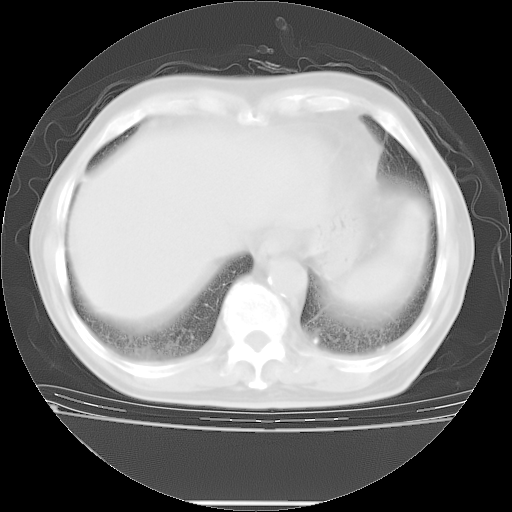

胸腹部CT,诊断意见:左上肺叶钙化灶、左侧胸膜局限性增厚并钙化、胆囊炎。描述部分肺组织呈磨玻璃样改变。